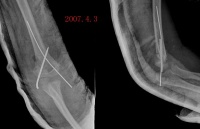

x线特征:受伤后不久可出现局限性肿快。伤后3-4周,在肿快内显示毛状致密象,其临近骨将显示骨膜反应。伤后6-8周,病变边缘部清楚地被致密骨质所包绕,而具有新生骨的外貌。软组织肿块的核心部有时显囊性变且逐渐扩大其内腔,到晚期而显出类似蛋壳状的囊肿。伤后5-6个月肿块收缩,因而肿块与邻近的骨皮质和骨膜反应之间显出x线透亮带。